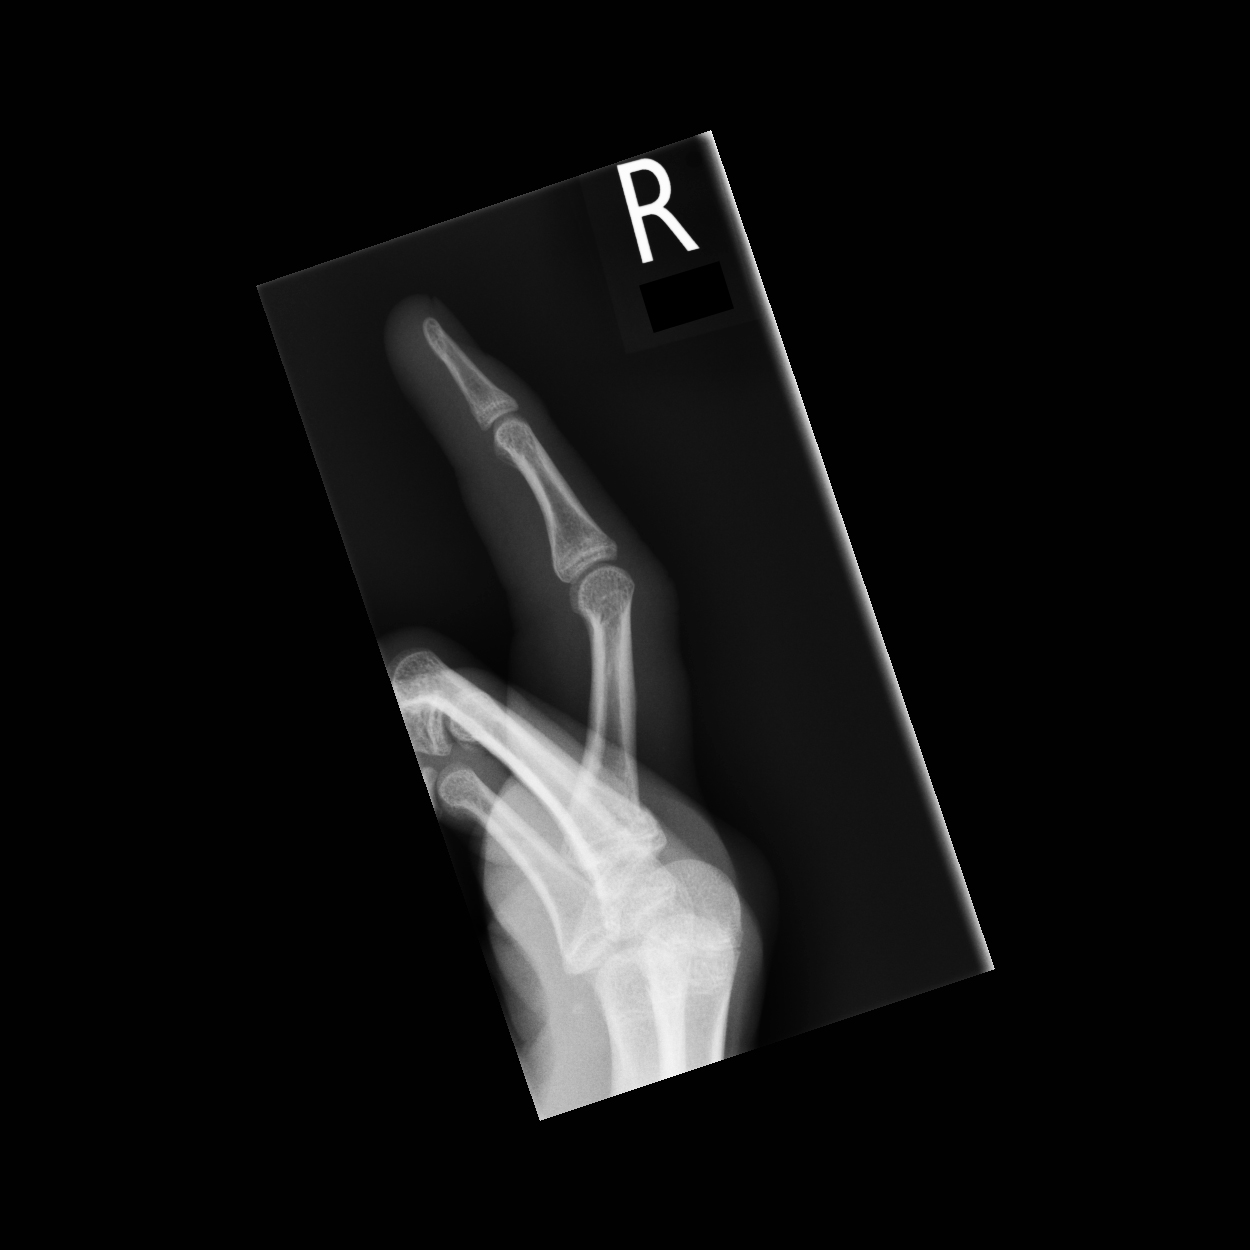

| 15 |

Abnormal fr pp |

Abnormal Right second proximal phalanx base fracture |

Correct |